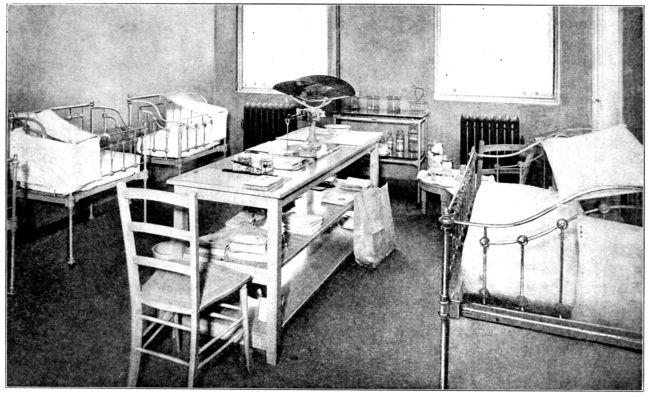

| 153. | Nursery at Manhattan Maternity Hospital | 465 |